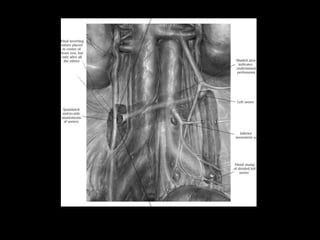

Diagnostico

• USG S-80%, E-85%

• UROGRAFIA ENDOVENOSA S-82 Y E-85